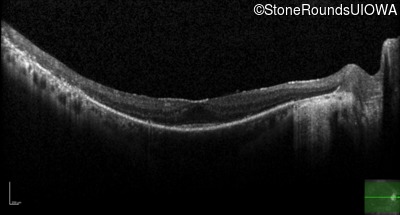

Optical Coherence Tomography - Left - 20/20 -2

Exemplar / OCT Stack